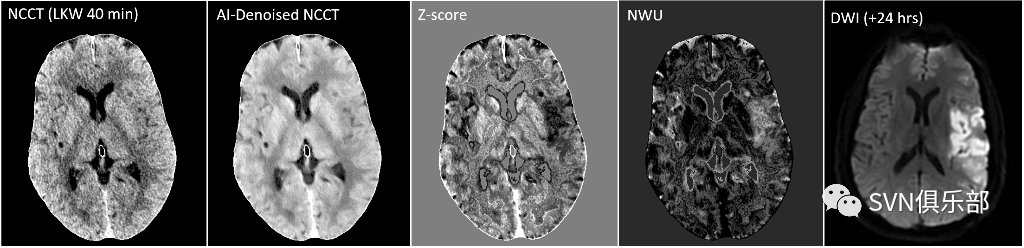

来自美国Houston Methodist Research Institute的Kelvin K. Wong带来的研究是关于平扫CT中评价脑净水摄取(Net water uptake, NWU)的技术。全脑NWU成像及Z-评分地图在大多数病例中得以验证。该研究中的Z-评分方法可显著改善急性卒中在NCCT上的可见性,足以鉴别脑出血及蛛网膜下腔出血。如下图为典型病例,可与磁共振弥散加权成像(DWI)相匹配。